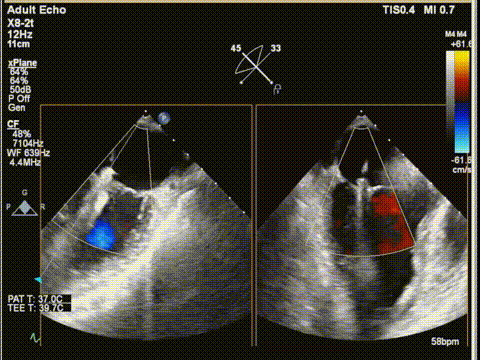

术前食道超声:

房颤,瓣环扩大的房性二尖瓣反流,反流主要集中在二区,二区后叶部分脱垂,后叶的长度16mm,前叶的长度是37mm。房间隔整体的条件可,从瓣环到拟定的卵圆窝顶部高度大概是41mm。

二尖瓣2区color

三尖瓣

三尖瓣反流以膈叶脱垂为主,反流主要集中在前叶和膈叶间,从中心区向边缘区的蔓延。后叶又有分了两个叶,分型上属于IIIb型的三尖瓣反流。

三尖瓣膈叶前叶

三尖瓣膈叶前叶color